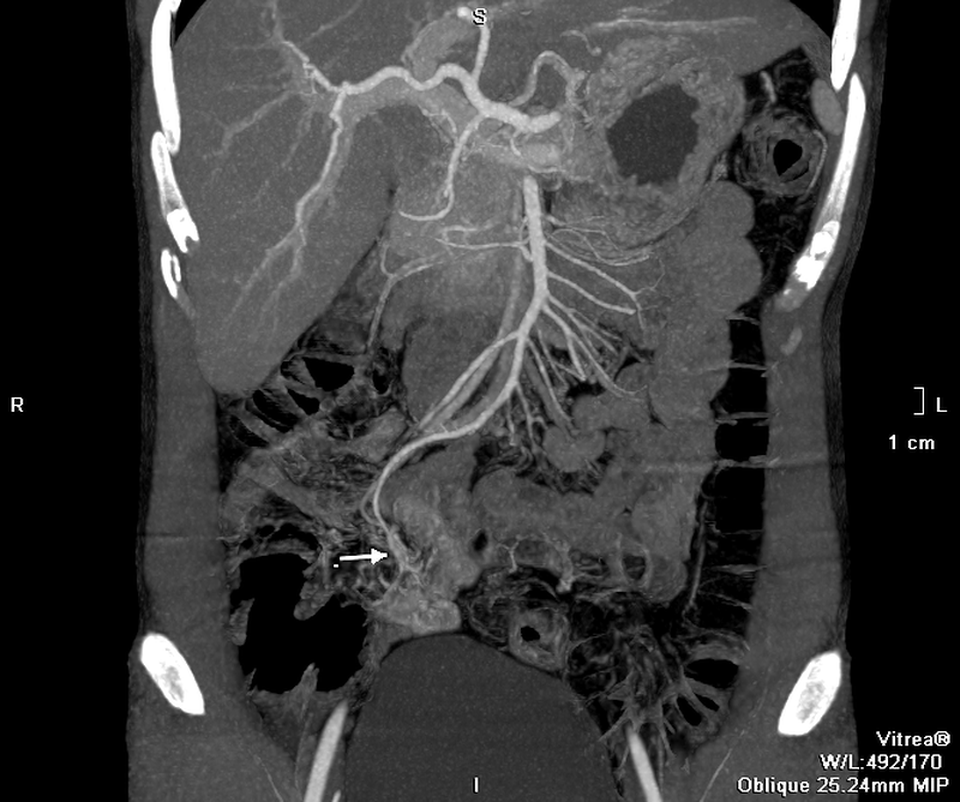

Kết quả chụp CT cho thấy bệnh nhân có búi dị dạng mạch máu trong lòng ruột, đang có dấu hiệu chảy máu. Đây là thủ phạm gây chảy máu kéo dài. Bệnh nhân được hội chẩn, điều trị khẩn cấp bằng phương pháp can thiệp mạch để nút búi dị dạng. Sau thủ thuật 24 giờ, bệnh nhân không còn triệu chứng chảy máu, hồi phục và xuất viện.